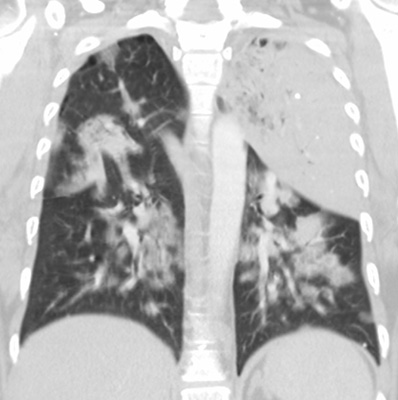

Scott WilliamsVascular AbnormalitiesVascular > Coarctation > ImagesApril 2, 2002Tumor ImagingThallium Tumor Imaging:April 2, 2002Vascular AbnormalitiesVascular > Dissection > ImagesApril 2, 2002Cardiac ImagingEquilibrium MUGAApril 2, 2002TumorTumor > Malignant > LungcancerApril 2, 2002Infections-InflammatoryInfect > Parasites > PCPApril 2, 2002Infections-InflammatoryInfect > Bacterial > LegionellaApril 2, 2002Infections-InflammatoryInfect > Fungus > Blasto > ImagesApril 2, 2002LymphoproliferativeLymph > PTLDApril 2, 2002AutoimmuneAutoimmune > PulmossificationApril 2, 2002Previous PagePage 72 of 265Next PageTop StoriesPractice ManagementHPI: Radiology attrition varies by gender, specialty, and practice typeContinuing workforce trends such as increasing subspecialization and practice consolidation could affect the attrition rate.Radiation Oncology/TherapyASTRO: Short prostate SBRT reduces side effects, but not PSA levelsRadiation Oncology/TherapyASTRO: STAR has role in managing VT in cardiac patientsCT5-year CTC screening interval is appropriate for colorectal cancerSponsor ContentDigital Innovations Shaping the Future of Radiology